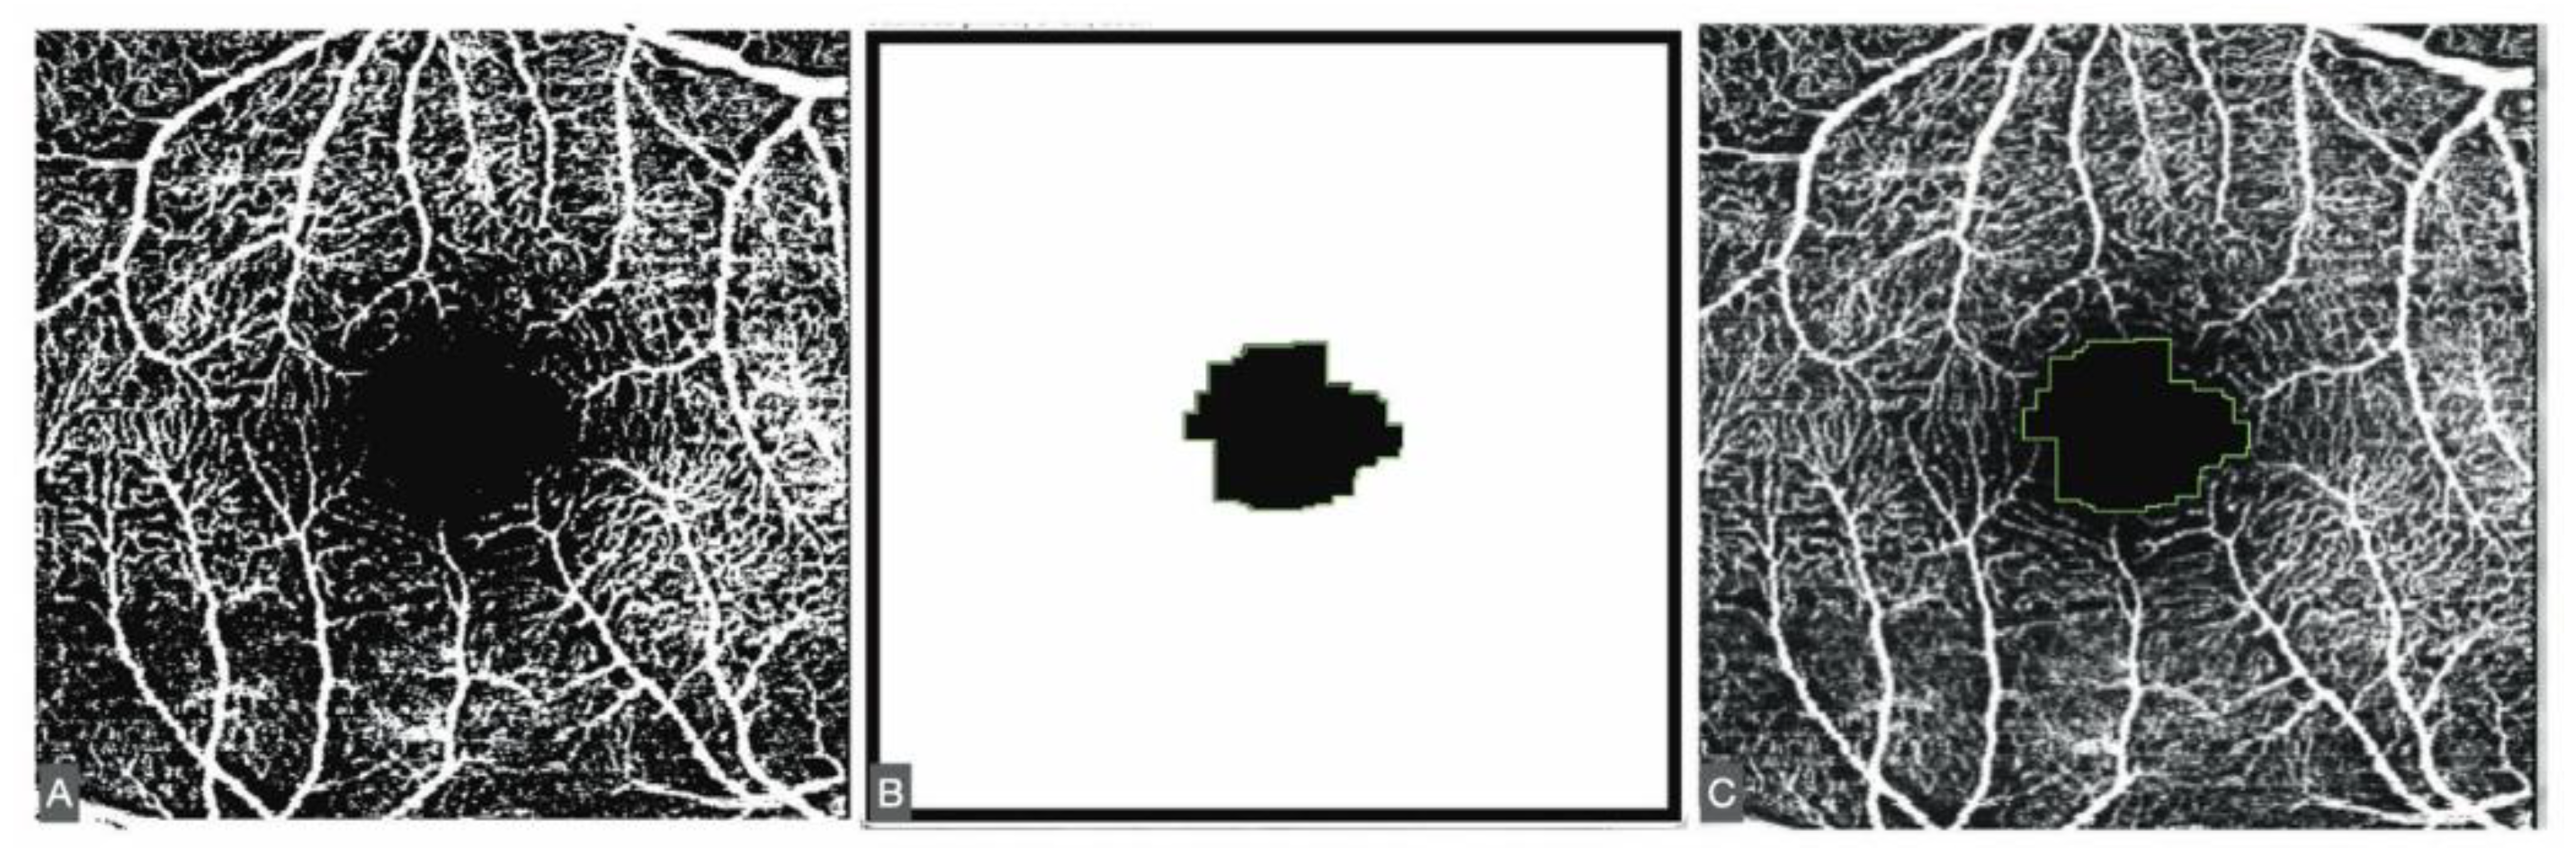

The FAZ was measured using a script adapted from Ishii [11]. Minor modifications were introduced, including adjustment of image size and the application of Otsu binarization [12], a local/global thresholding method that reduces artifacts compared with other binarization algorithms (Figure 1).

Figure 1. A. Otsu binarization of the SVP. B. The results of the ImageJ script. C. Fit of the result of the script in the 8-bit former image.